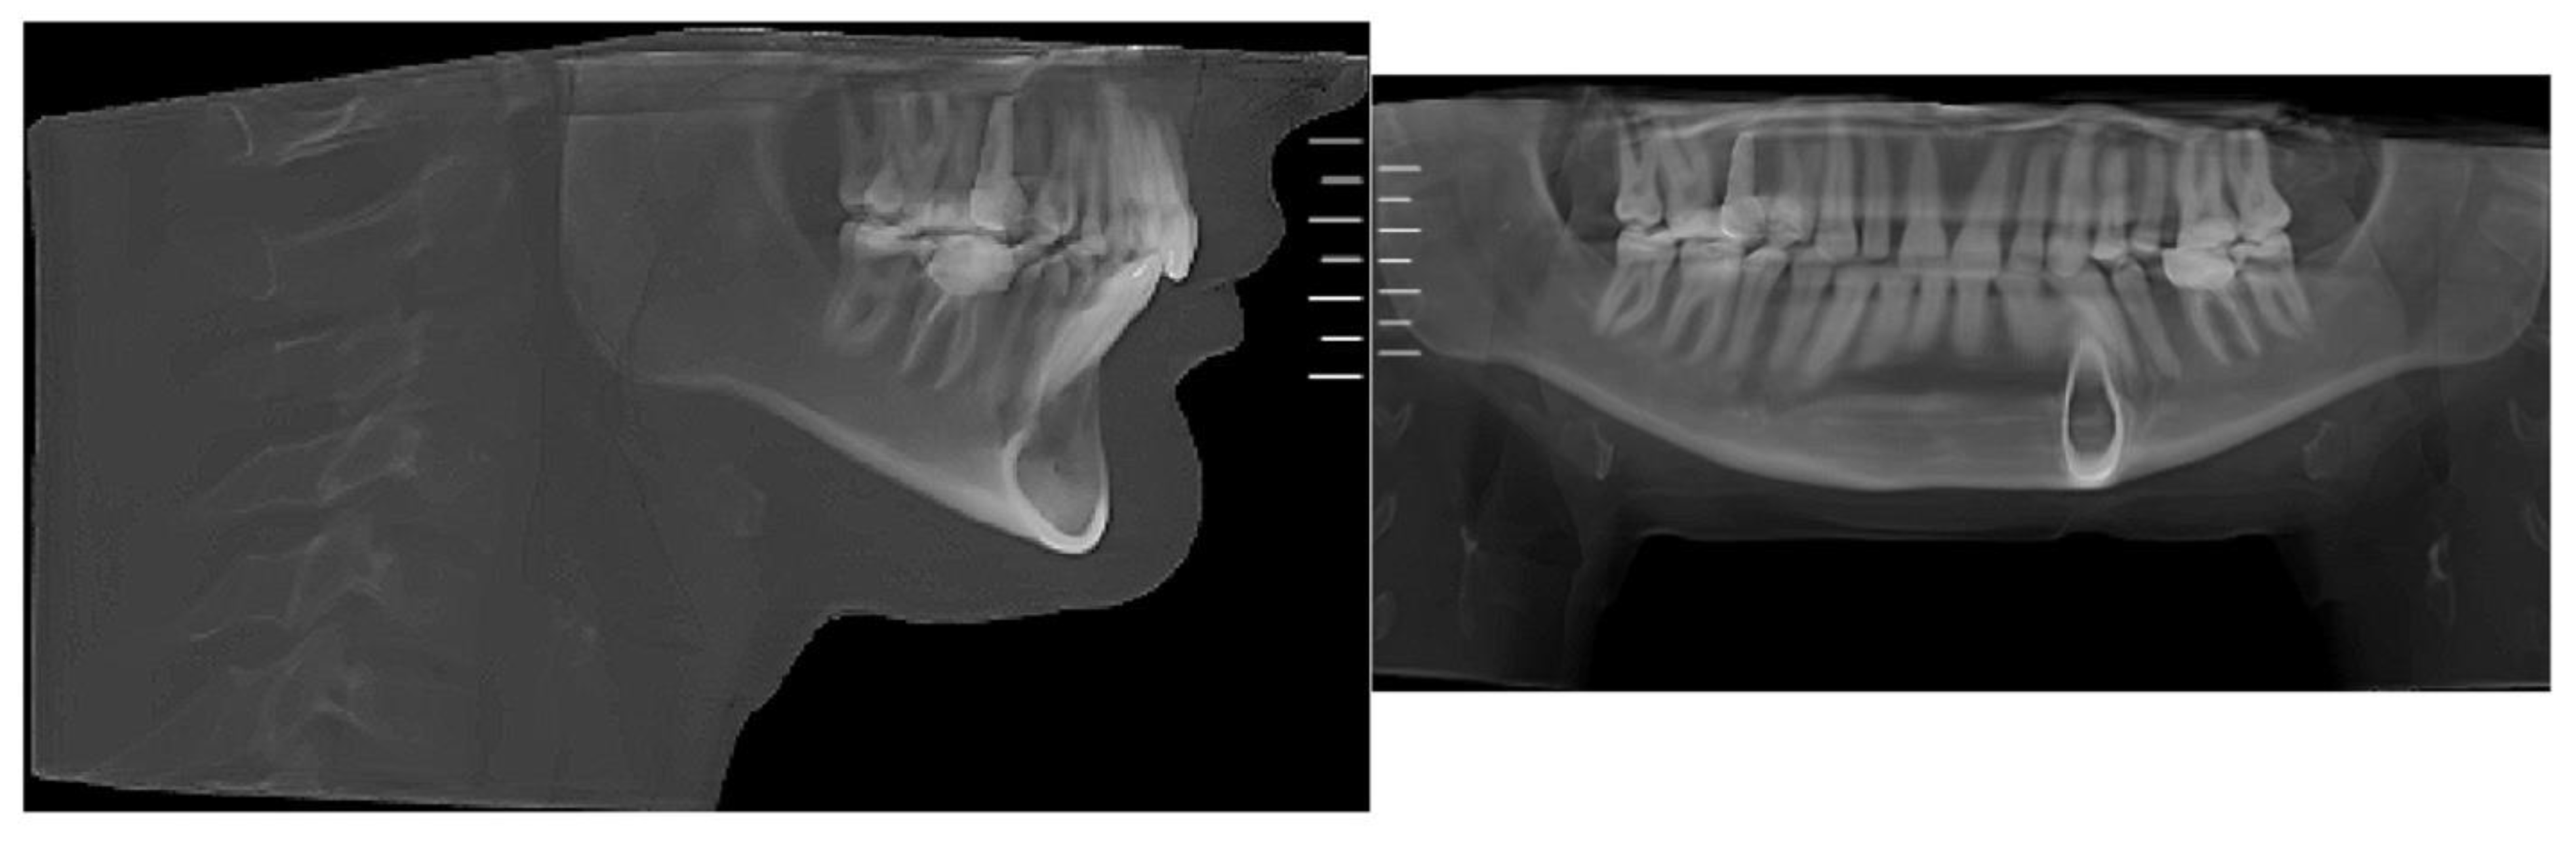

Figure 3. Pre-treatment lateral cephalometric and panoramic radiographs taken in habitual occlusion.

Lateral cephalometric radiograph and panoramic radiograph immediately after expansion shown in Figure 9.